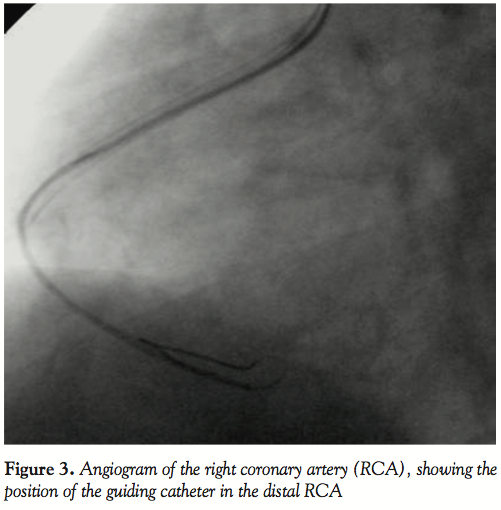

followed by infusion of 0.125 µg/min for 12 hours), the patient underwent percutaneous transluminal coronary angioplasty (PTCA) of the RCA. The RCA was engaged with a 7 Fr Judkins right guiding catheter (Boston Scientific, Natick, Massachusetts) and the lesion was profiled in various views. The lesion was crossed with a Balance Middle Weight (BMW) Universal™ guidewire (Guidant Corporation, Temecula California) and dilated with a 2.5 x 10 mm Amadeus balloon (Eurocor, Bonn, Germany). Postdilatation injection revealed a large ectatic RCA loaded with thrombus extending from the ostium to the distal vessel with no significant stenosis (except for nonvisualization of the PLV) and TIMI-1 flow (Figure 2). In view of the large thrombus burden, an X-sizer thrombectomy/thrombosuction device (Model No. XS-CS 1200-60; EndiCOR Medical Inc., San Clemente, California) with a cutting diameter of 2.0 mm was passed up to the distal RCA and thrombosuction was done from distal to proximal RCA. Post-thrombosuction angiogram, however, revealed no appreciable change in the thrombus burden. Therefore, a 3 Fr Tracker perfusion catheter with side holes (Target Therapeutics, Fremont, California) was passed over the guidewire up to the distal RCA, over which a 7 Fr right coronary guiding catheter was

maneuvered up to the distal RCA (Figure 3). Manual suction of thrombus was then tried by attaching it to an airtight, 20 ml luer-lock syringe and gradually withdrawing it from the distal to proximal RCA. Maintaining negative suction, the guiding catheter was slowly withdrawn from the RCA and the femoral sheath. Flushing the guiding catheter outside revealed small pieces of thrombi. Angiogram following this maneuver showed appreciable reduction of the thrombus burden in the proximal RCA, but the distal RCA was still loaded with thrombus (Figure 4). The same maneuver of advancing the guiding catheter over a guidewire and Tracker catheter into the distal RCA and aspiration of thrombus was repeated. However, external flushing of the guiding catheter did not reveal any thrombi and repeat angiogram was identical to that obtained after the first aspiration. As TIMI-2 flow was achieved, we thought of tackling the residual thrombus by pharmacological means. Infusion of abciximab was continued for 12 hours. Infusion of unfractionated heparin (1,000 U/hour) was continued for 24 hours. The patient was kept under invasive hemodynamic monitoring in the coronary care unit. A check angiogram at the end of 24 hours revealed TIMI-3 flow with marked reduction of the thrombus burden in the proximal RCA and persistent large thrombus in the distal portion (Figure 5).